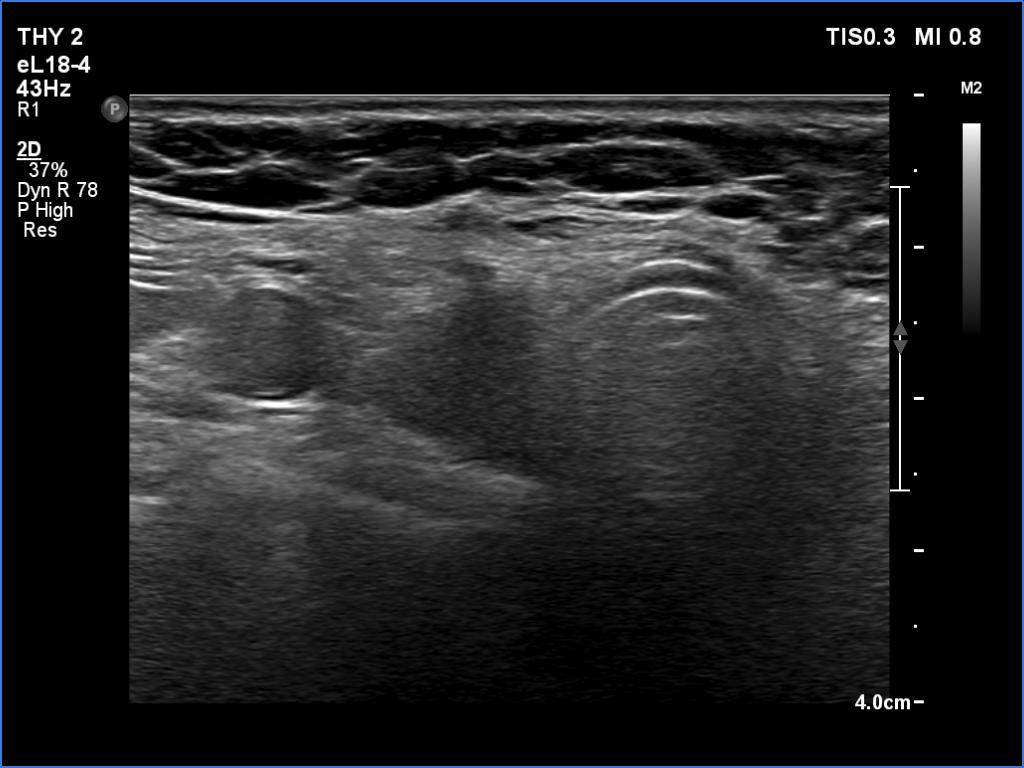

First examination (first and second rows of images):

Clinical data: A 62-year-old woman was operated on Graves' disease 15 years ago. She did not require replacement therapy. She was now referred for an evaluation of palpation and 7 kg weight loss and recurrent nodule described on ultrasonography.

Ultrasonography. A diffusely hypoechogenic thyroid was found with small more hypoechogenic areas. The hypoechogenic area was surrounded with echonormal tissue. This pattern was interpreted falsely as a nodule by a previous examiner. The vascularization was average.

Comment. It is worth analyzing the ultrasound presentation - a large hypoechogenic area is surrounded with a thick echonormal rim. Although this pattern seems to be a nodule, it is one of the most characteristic appearances of a subtotally resected thyroid.